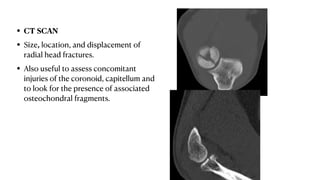

• CT SCAN

• Size, location, and displacement of

radial head fractures.

• Also useful to assess concomitant

injuries of the coronoid, capitellum and

to look for the presence of associated

osteochondral fragments.